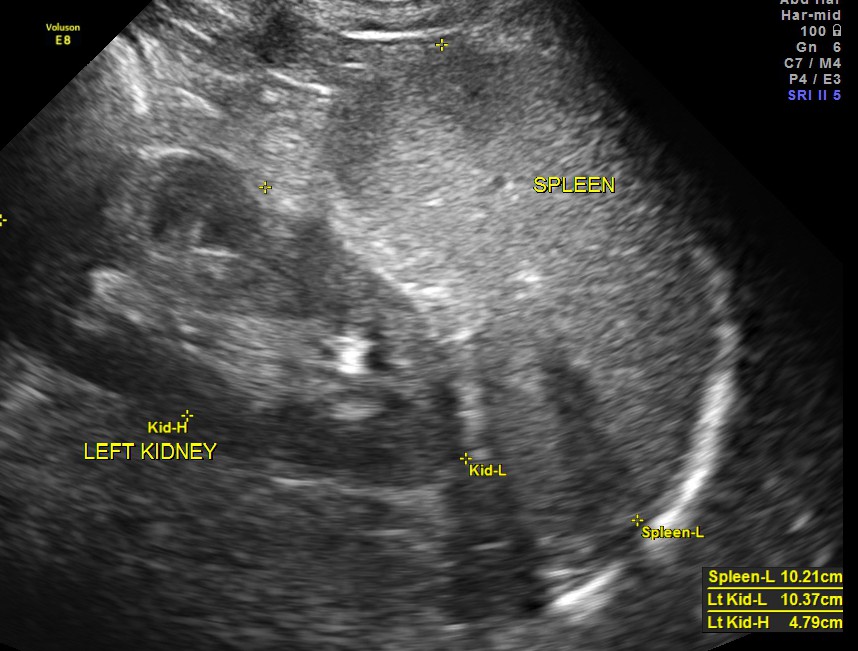

The scan was otherwise normal.